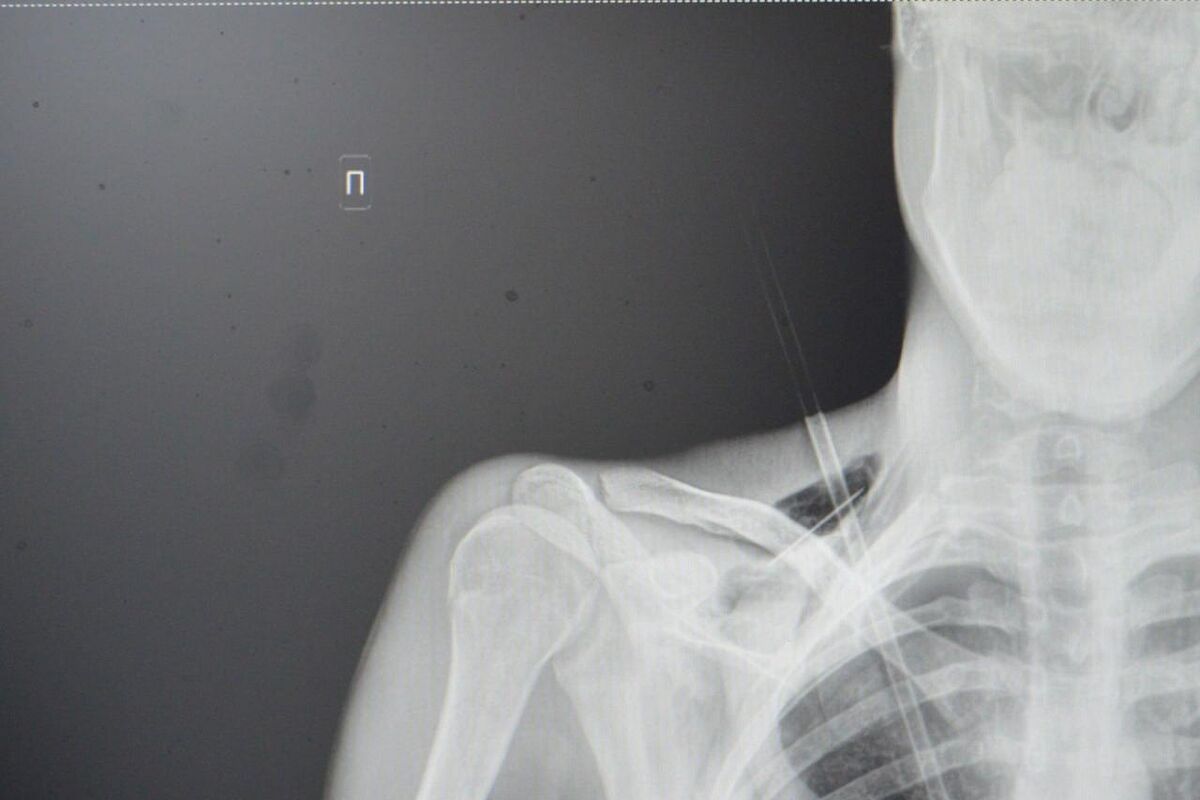

Как рассказали медики, юноша поступил в больницу на скорой со стрелой в грудной клетке. Он рассказал, что вместе с девушкой занимался стрельбой из спортивного лука, когда стрела срикошетила от дерева и вонзилась ему в грудь.

После госпитализации пациента отправили на экстренную операцию: стрела прошла между ключицей и правым ребром, пробив верхушку легкого на шесть сантиметров. По словам врачей, юноше повезло, что предмет не задел подключичную артерию или вену.